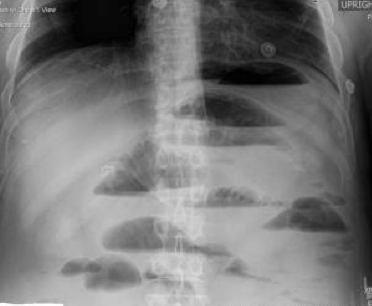

What is likely going on here?

Young woman. Hx of abdominal pain and diarrhea. Now presents with worse pain, abdominal distension and vomiting.

What is going on? Tests?